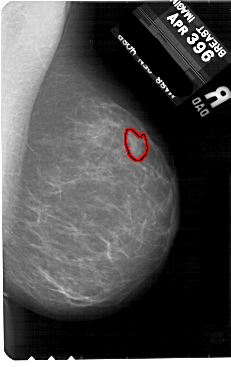

FILE: A_1886_1.RIGHT_CC.OVERLAY

TOTAL_ABNORMALITIES 1

ABNORMALITY 1

LESION_TYPE MASS SHAPE IRREGULAR MARGINS ILL_DEFINED

ASSESSMENT 4

SUBTLETY 3

PATHOLOGY BENIGN

TOTAL_OUTLINES 1

BOUNDARY

RIGHT_CC LINES 5491 PIXELS_PER_LINE 3211 BITS_PER_PIXEL 12 RESOLUTION 43.5 OVERLAY